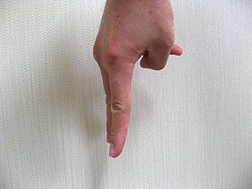

下の写真をご覧下さい。

正面から撮影した手ですが、指が2本見えています。

そして次の写真をご覧下さい。違う方向から撮影したら指は3本うつっています。

さらに一本目と二本目との間隔は開いていますが、二本目と三本目との間隔はほとんどないことがわかります。このようなことが現実に歯科の治療現場で起きているのです。

つまり、先ほども申し上げたように「開いて開けてみないとわからない」「インプラントを埋めてみないとわからない」ということです。手術の翌日、患者さまの元気そうな顔を見て内心ホッとしているのが現状なのです。